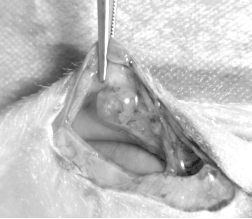

1、生殖器官外观:小鼠生殖器官在不同动情周期阶段有变化,如子宫颜色和大小、卵巢大小等,但观察需解剖小鼠,会造成伤害。

以下便是我们技术员辛勤劳作的结果,供大家参考: